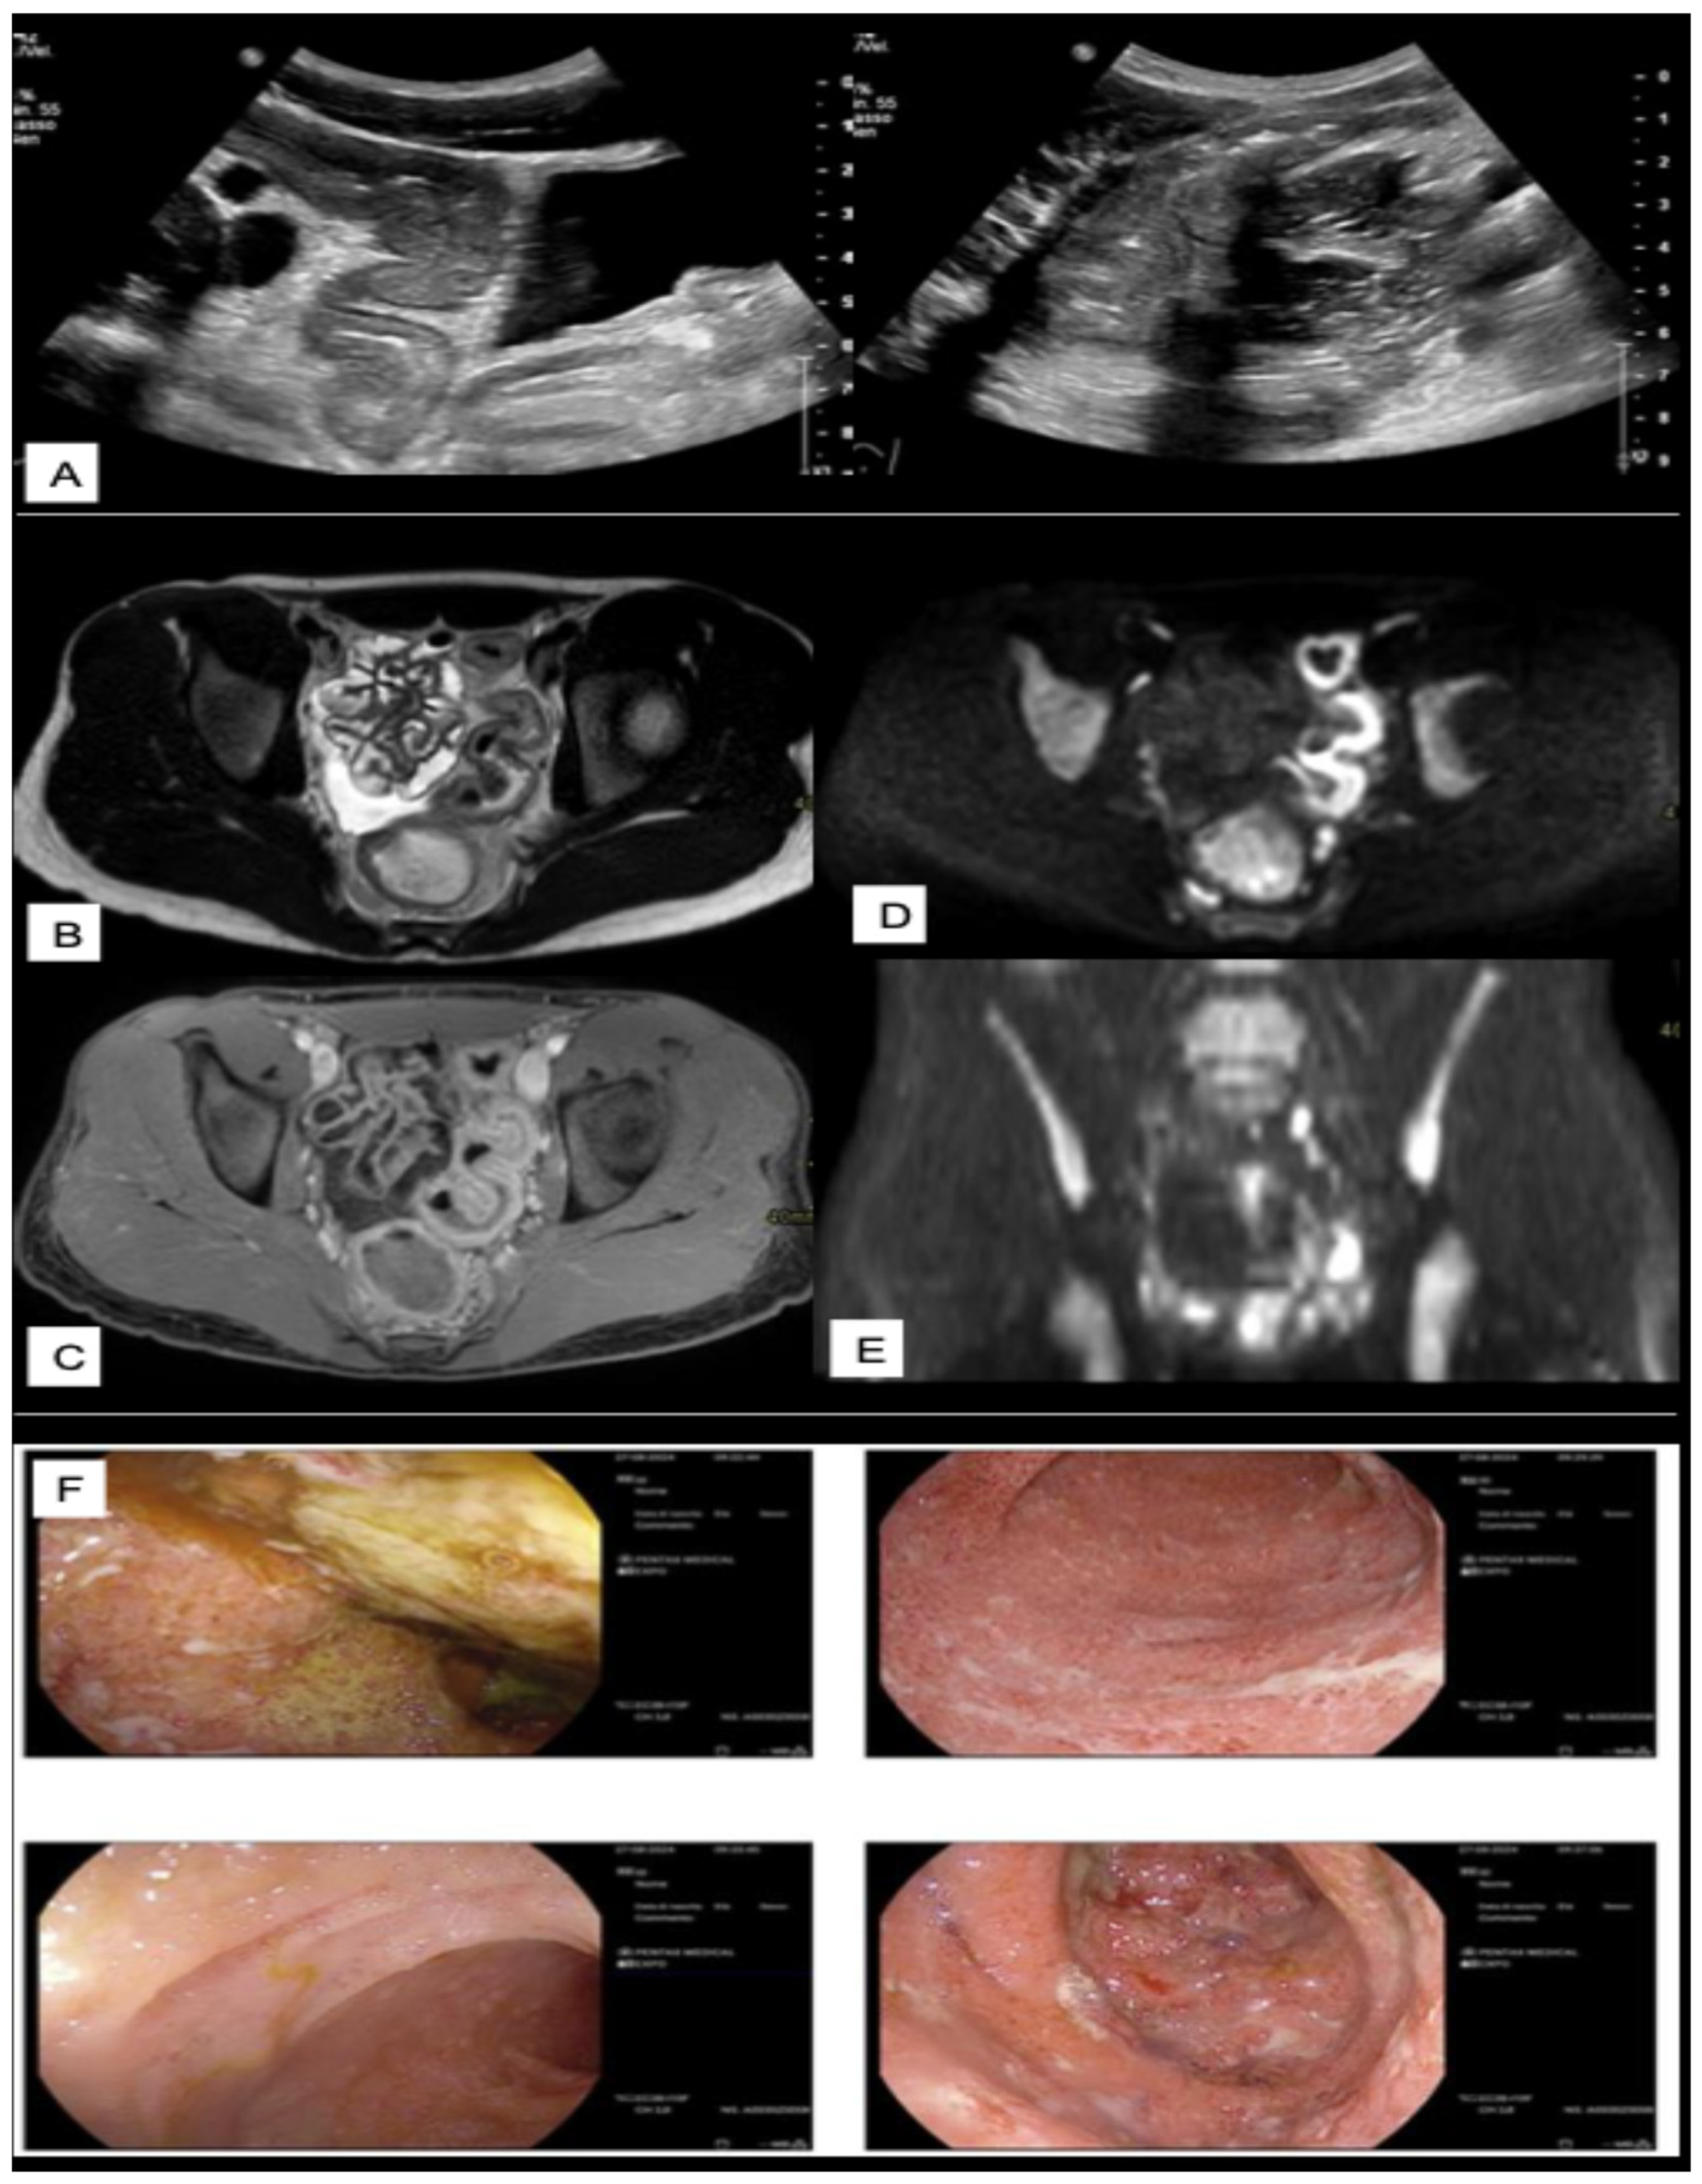

3.4.2. Typical MRI Findings in Crohn’s Disease

3.4.3. Typical MRI Findings in Ulcerative and Indeterminate Colitis

3.4.4. Diagnostic Performance of MRI vs. Endoscopy and Histology